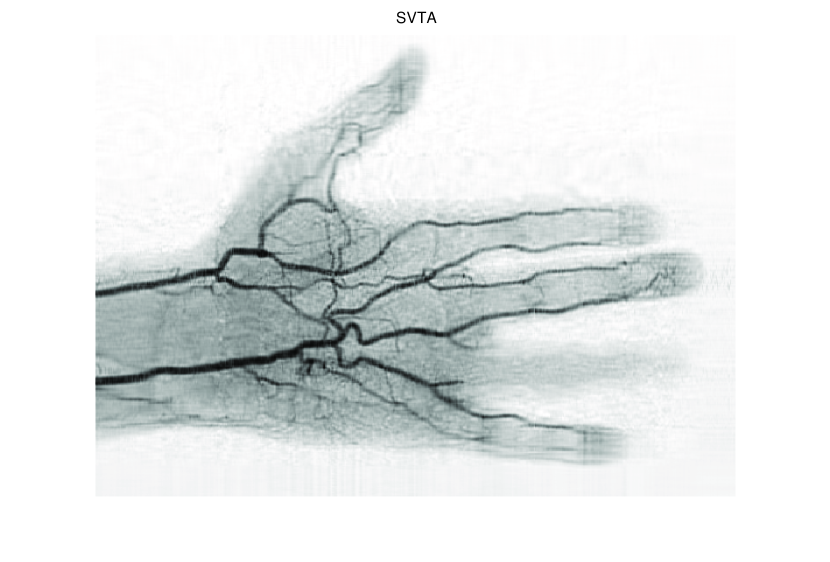

In this subsection, we demonstrate performances of ISVTA on image inpainting problems. The ISVTA is tested on some medical grace images (255×192255192255\times 192 Brain angiography image (BAI), 395×549395549395\times 549 Hand angiography image (HAI) and 419×400419400419\times 400 Intracranial venous image (IVI)). We use the SVD to obtain their approximated low-rank images with rank r=30,40,30𝑟304030r=30,40,30, respectively. Numerical results of ISVTA for theses low-rank image inpainting problems are reported in Table 5, 6, 7, 8.

Figure 4: Original 395×549395549395\times 549 HAI and its approximation with rank 40.

Figure 7: Comparisons of ISVTA, SVTA and SVPA for recovering the approximated low-rank HAI with SR=0.40.